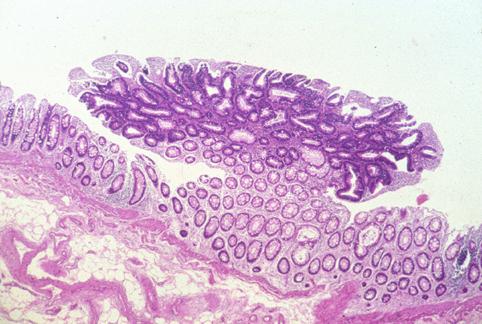

가족성 대장 용종증(Gardner 증후군)에 나타난 표면함몰형(IIc형) sm조기대장암

악성 상피성종양/선암

대장/직장

마이크로

1~9